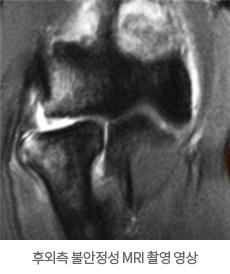

MRI를 찍어보면 파열된 인대 등을 진단할 수 있습니다.

후외측 불안정성 MRI 촬영 영상